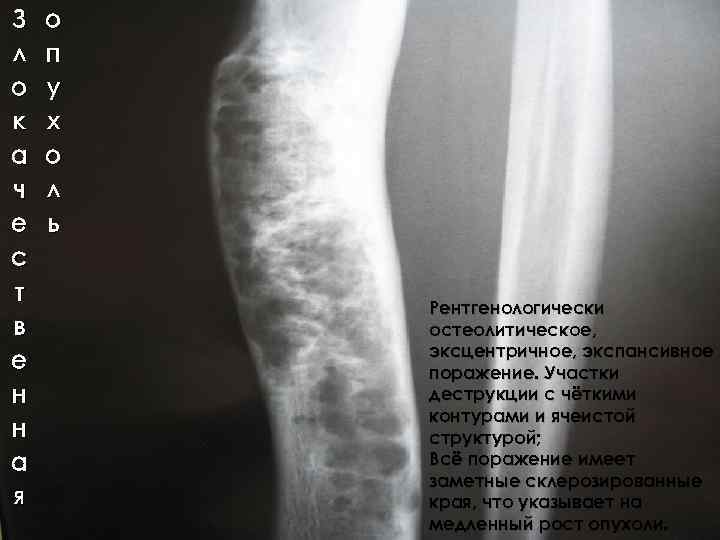

З л о к а ч е с т в е н н а я о п у х о л ь Рентгенологически остеолитическое, эксцентричное, экспансивное поражение. Участки деструкции с чёткими контурами и ячеистой структурой; Всё поражение имеет заметные склерозированные края, что указывает на медленный рост опухоли.